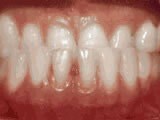

This adult patient, age 25, required braces and jaw surgery to correct his severe overbite, with treatment taking two years. His problem could have been corrected without surgery if he had been treated before he was a teenager